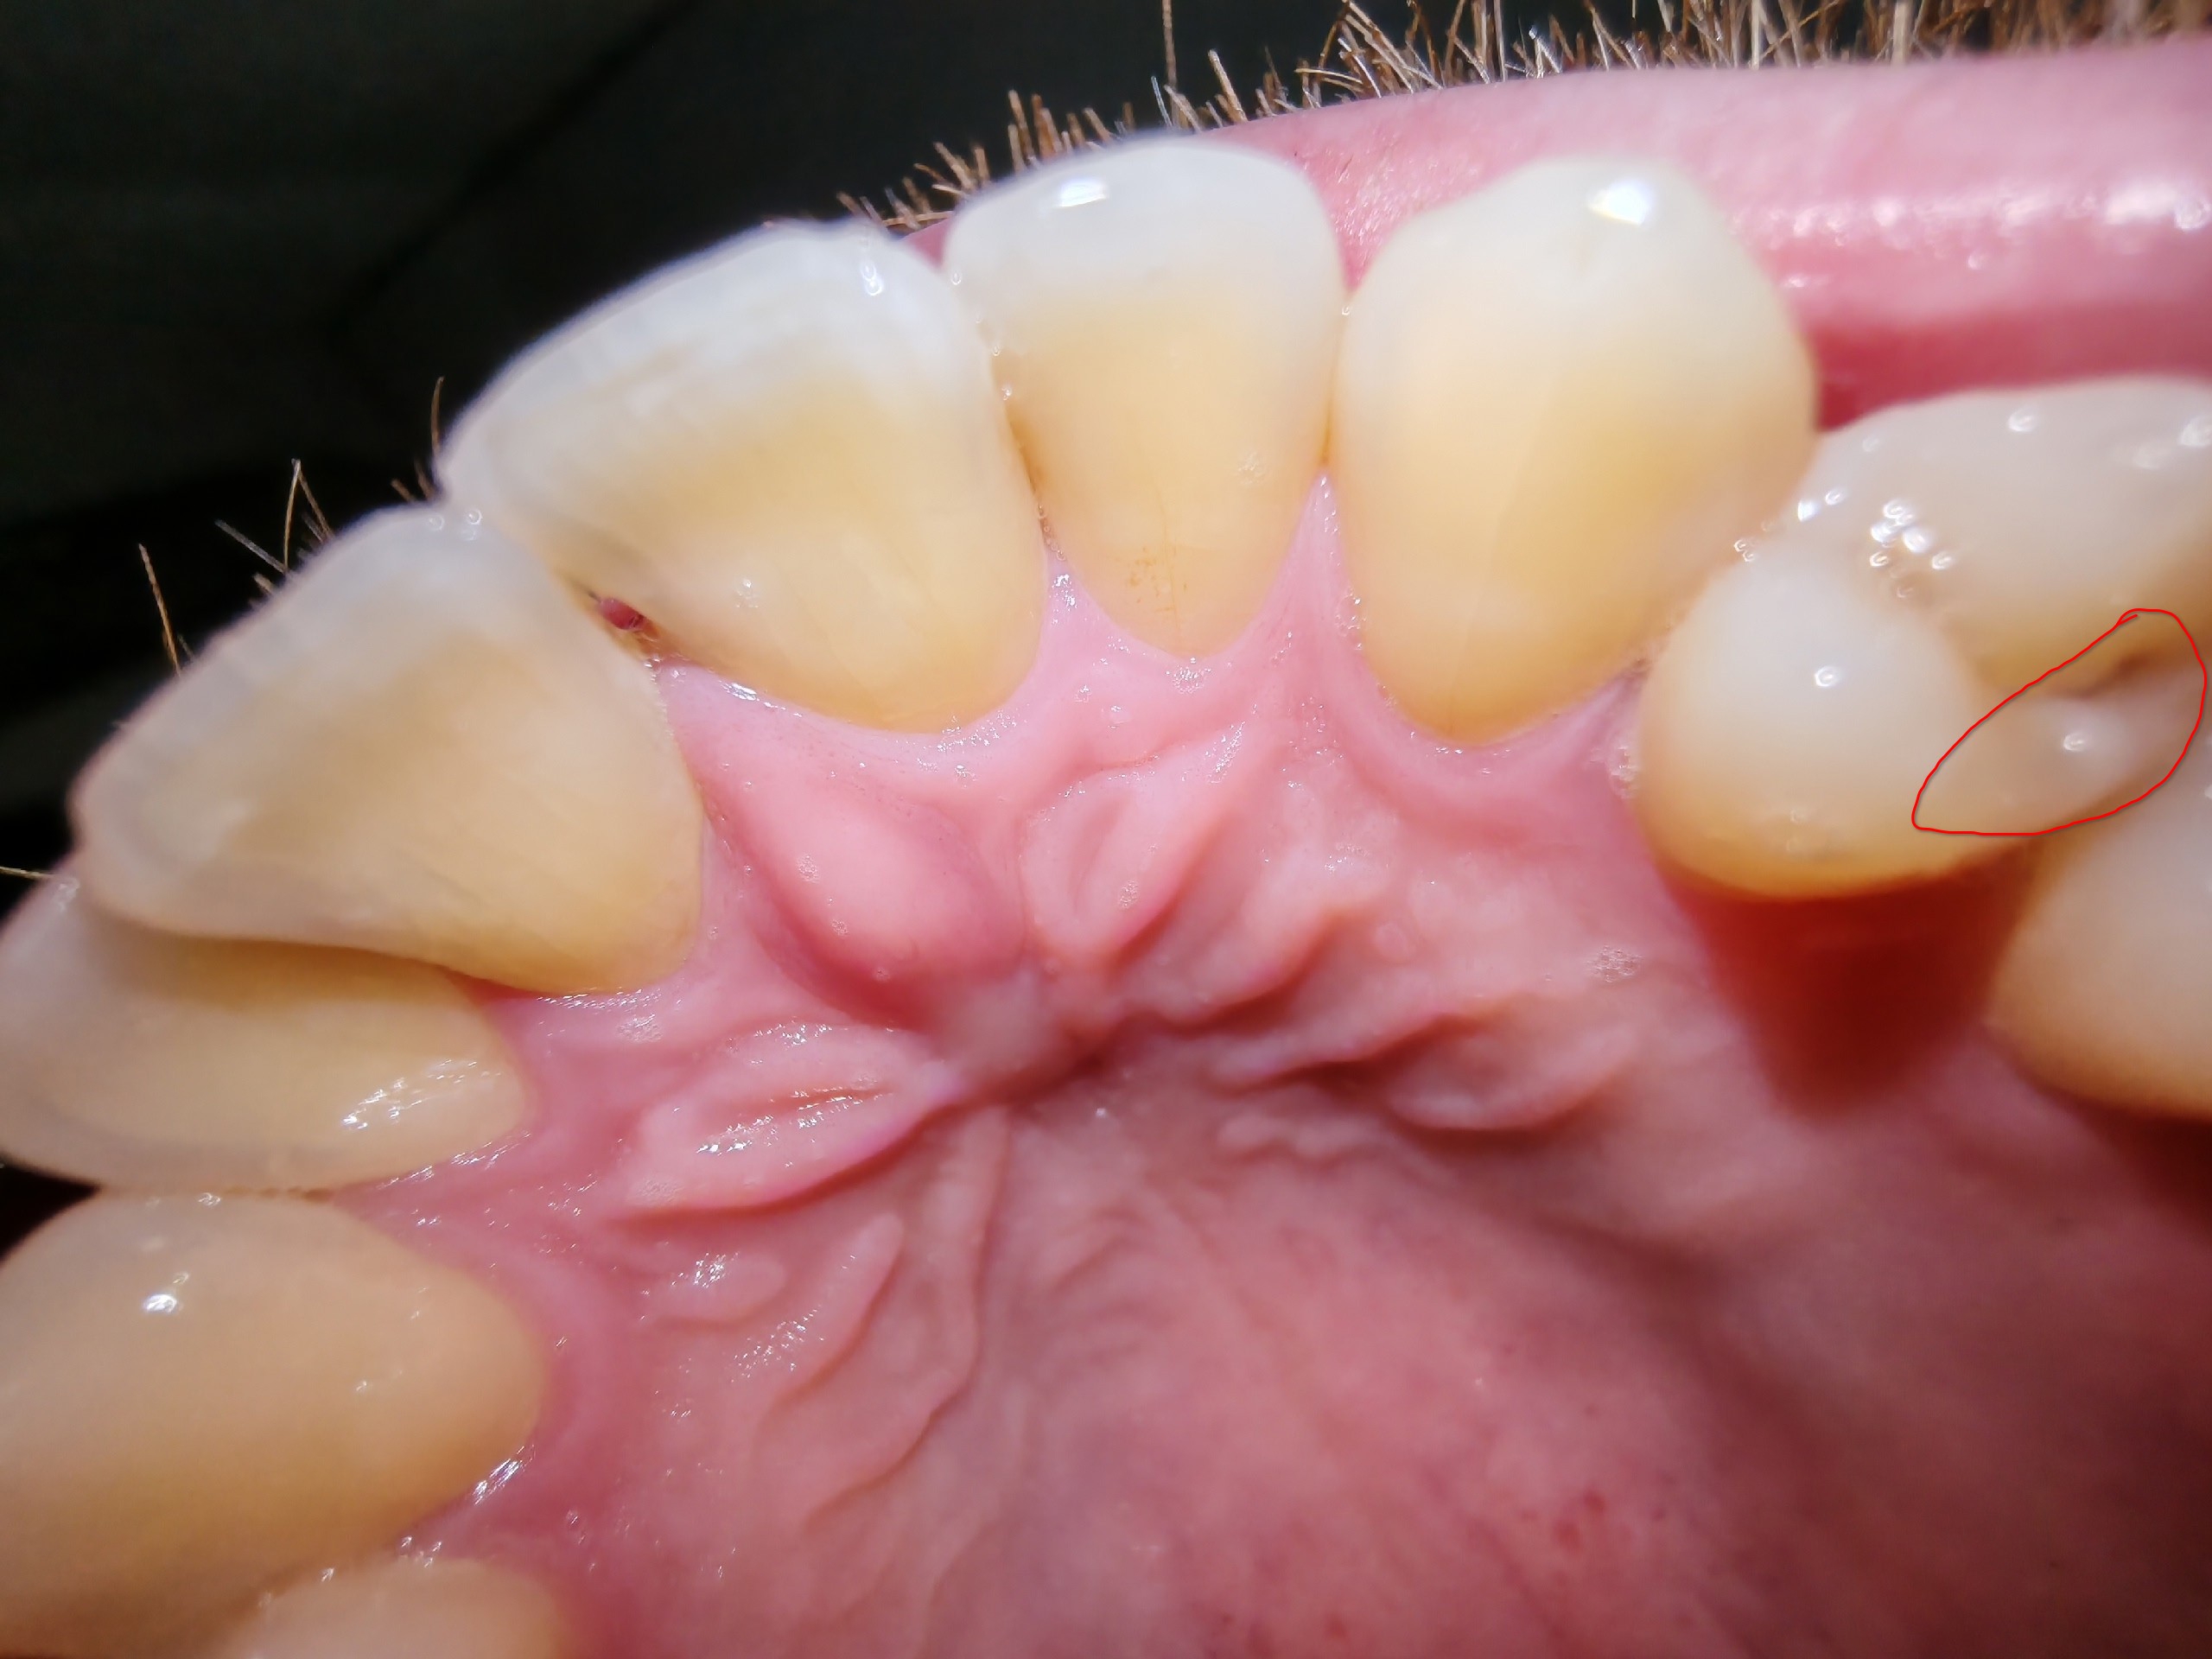

>>331449435 На одном из передних зубов появилась такая трещина, пошел к стоматологу, тот сказал, что может и до конца жизни не развалится. Через пару месяцев зуб рассыпался. На втором тоже трещинки есть, уже давно и пока, вроде, норм.